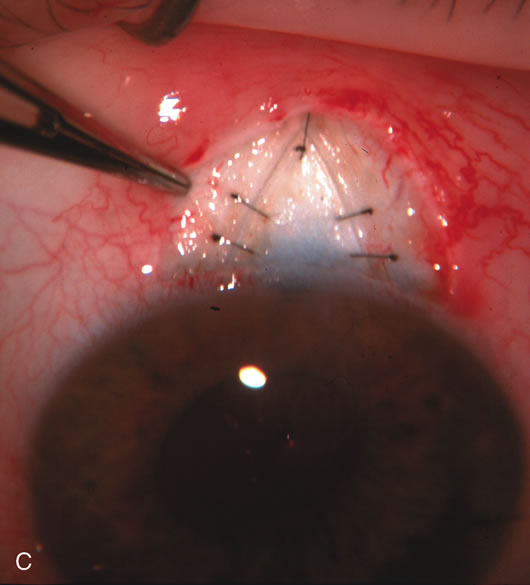

Fig. 3. Partial bleb failure following clear corneal phacoemulsification with foldable IOL. A. Preoperative bleb appearance prior to temporal lens extraction. Preoperative IOP was 12 mm Hg on no antiglaucoma medications. Time from 5-FU trabeculectomy surgery to lens extraction was one year. B. Bleb appearance 2 months after clear corneal cataract surgery with topical anesthesia. Following lens extraction, increased vascularity was noted along with decreased size of the filtering bleb. IOP increased to 20 mm Hg as early as 2 weeks after surgery, necessitating topical antiglaucoma therapy. C. High magnification view of bleb before lens extraction demonstrates diffuse pale bleb. D. High magnification view of bleb 2 months after surgery. There are vessels surrounding the nasal side of the bleb and the overall bleb size is smaller.

Fig. 7. Phacotrabeculectomy adjacent to a failed filter in cataractous eye. The ability to combine small-incision cataract extraction with trabeculectomy all through the same incision adjacent to the failed filter allows the surgeon to work in a familiar superior area. Avoiding incisions into the existing bleb decreases conjunctival buttonholes, hypotony, operating room time, and subconjunctival bleeding. A. Appearance of failed bleb with exposure of superior temporal quadrant gained with a corneal traction suture. B. Prepare a limbus-based conjunctival flap and a scleral flap. C. This bleb is at high risk to fail again justifying the need for MMC, 0.2 mg/cc applied on a pledget for 4 minutes. D. Insert the keratome and perform phacotrabeculectomy in the usual fashion.